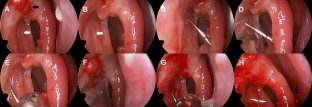

Fig. 1

Fig. 2